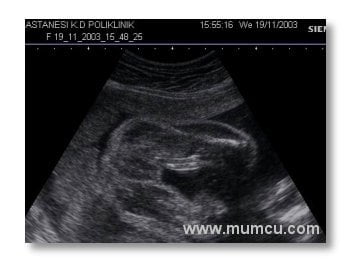

6 haftalık ikiz gebelik

Vajinal ultrasonografi